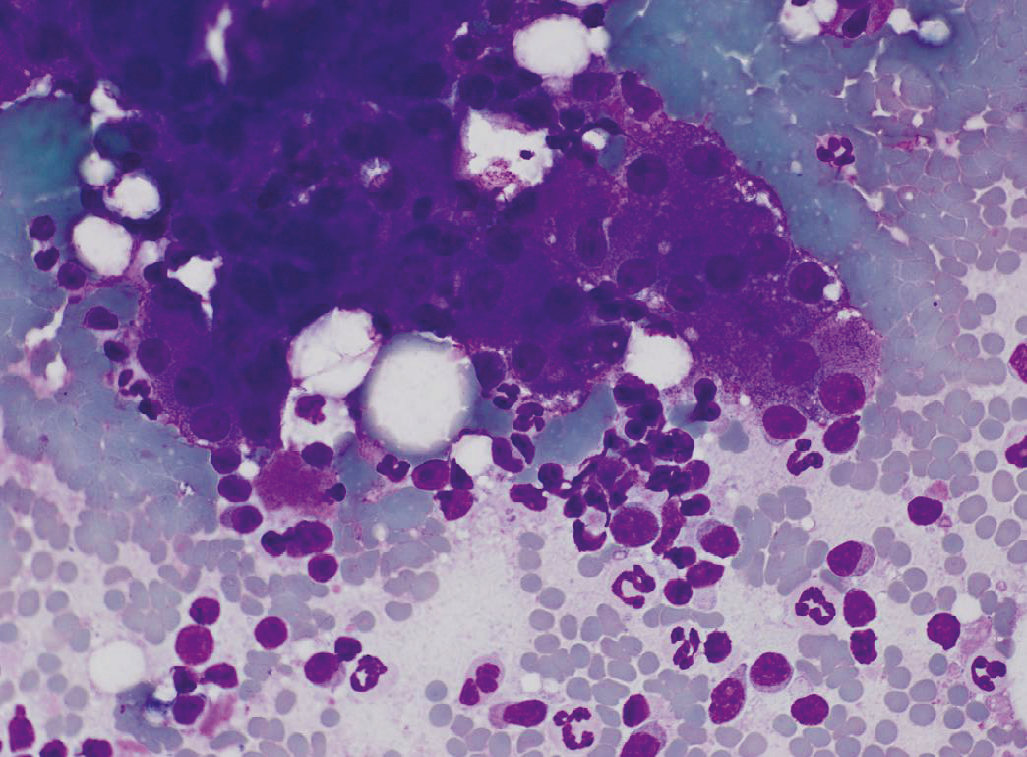

胰腺在多种至关重要的代谢功能中担负着重要的角色。胰腺外分泌部会分泌消化酶,在营养成分的利用过程中必不可少。胰腺外分泌部的炎症和退行性病变在犬猫也十分重要。